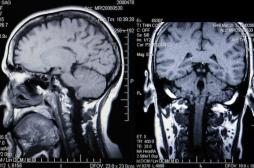

LES MALADIES